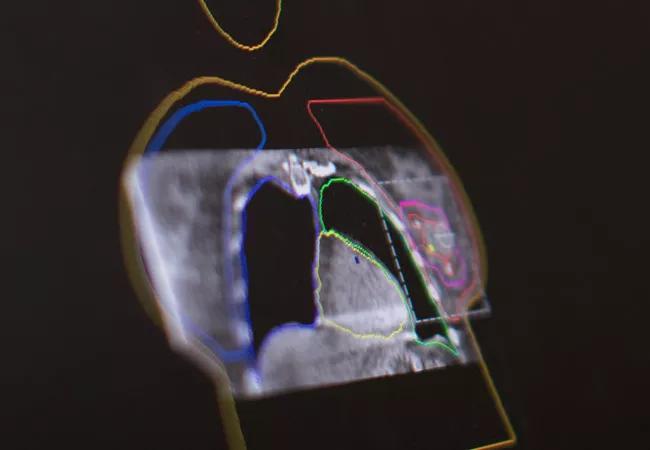

Sparing the Heart in Breast Cancer Radiotherapy

When Chirag Shah, MD, became a radiation oncologist in 2007, almost all breast cancer patients had one option: five to six weeks of daily, whole-breast/chest-wall radiation, regardless of surgical type (mastectomy or lumpectomy). A mere decade later, thanks to advances in the field in part refined at Cleveland Clinic Cancer Center, patients can choose among several options for radiotherapy, many of which are far safer for the heart.

Cardiac toxicity after radiotherapy can include a range of conditions, from valvular disease to coronary artery disease and arrhythmias. Accelerated partial-breast irradiation (APBI) is a cardiac and pulmonary dose-sparing technique that allows appropriately selected patients with early-stage breast cancer to complete adjuvant radiation in two weeks or less following breast conserving surgery. To date, multiple randomized trials have demonstrated no difference in rates of recurrence or survival with APBI delivered using brachytherapy or external beam radiation techniques.

One method of delivering APBI is intensity-modulated radiation therapy (IMRT), a highly precise form of radiotherapy. IMRT is commonly used to treat prostate, head and neck and central nervous system cancers. Dr. Shah’s team is refining its use in breast cancer to deliver partial breast irradiation. IMRT can deliver higher doses with fewer side effects and reduced treatment toxicity, but it does require more planning than other traditional methods.

While techniques targeting a smaller volume area like APBI and intraoperative radiotherapy (IORT) are important for reducing cardiac exposure to radiation, Cleveland Clinic Cancer Center also employs a variety of additional techniques to further minimize cardiac toxicity after radiotherapy for patients requiring more comprehensive radiation therapy to the whole breast/chest wall.

“The timing of radiotherapy with respect to the breathing cycle can make a clinically significant difference in the dose the heart receives,” says Dr. Shah. “We incorporate this timing into our treatment planning by having patients perform a deep inspiratory breath hold during the CT scan used for planning, and we can estimate doses to the heart and observe the benefit with DIBH as compared to without.” For daily treatment, the active breathing control (ABC) system tracks the patient’s breathing, using the amount of air inspired as a surrogate for the distance between the heart and the breast. At the designated distance (based on inspiratory volume), the radiation is delivered. Surface-guided radiation therapy is used to ensure that the technique is delivered with accuracy.

Prone patient positioning allows the breast to fall away from the chest wall, increasing the distance of the radiation beam from the heart and reducing cardiac dose. “It’s especially useful for patients with large breasts,” says Dr. Shah. “It doesn’t make as big of an impact as using breathing techniques such as DIBH, but it can be beneficial for a subset of patients.”

Heart blocks represent another strategy to reduce cardiac dose. During treatment planning, Dr. Shah and the team block the heart using computer-programmed leaves inside the linear accelerator. The advances in programming allow blockage of the left ventricle without sacrificing dosing to the breast/chest wall. Using blocks allows for further reduction in heart dose and can be used with DIBH and other techniques.

Cardiac dosing 50 percent below national average

The team is preparing data for publication showing that cardiac doses at Cleveland Clinic are lower than the national standard by more than 50 percent. “If you exclude the most complicated cases treating targets near the heart, the average is closer to a 75 percent reduction,” says Dr. Shah. “We’re really proud of what we’ve been able to achieve for our patients using a combination of cardiac-sparing techniques.”